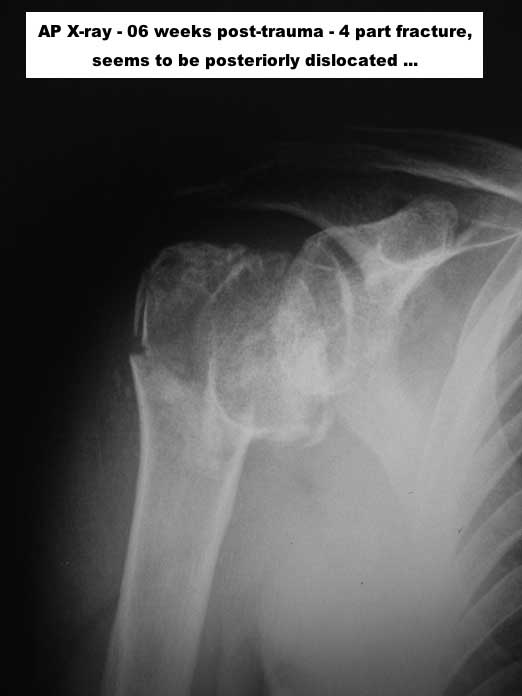

При переломах проксимального плеча, кроме обычных рентген снимков, необходимо сделать КТ исследование. Особенно 3D реконструкция, которая даст полную информацию о расположении фрагментов, потому что от количества фрагментов зависит тактика лечения. Переломы из 4х фрагментов приведет к остеонекрозу и поэтому прямое показание к эндопротезированию. Переломы с меньшим количеством фрагментов успешно могут быть синтезированы!

I cannot actually recognize, very much as I suppose you cannot either, which was the initial injury pattern and thus its classification. Either both tuberosities did not split apart as it sometimes happens or they have united afterwards.

Maybe a CT / MRI would afford more information about the actual fragments morphology and even perfusion in order to consider a reconstruction with or without an osteotomy between both tuberosities. It’s quite difficult believing in a full reconstruction due to the limited size and situation of the head, but one never knows, … mainly if you are a specially gifted surgeon and you’ve got a full bag of lucky vibrations.